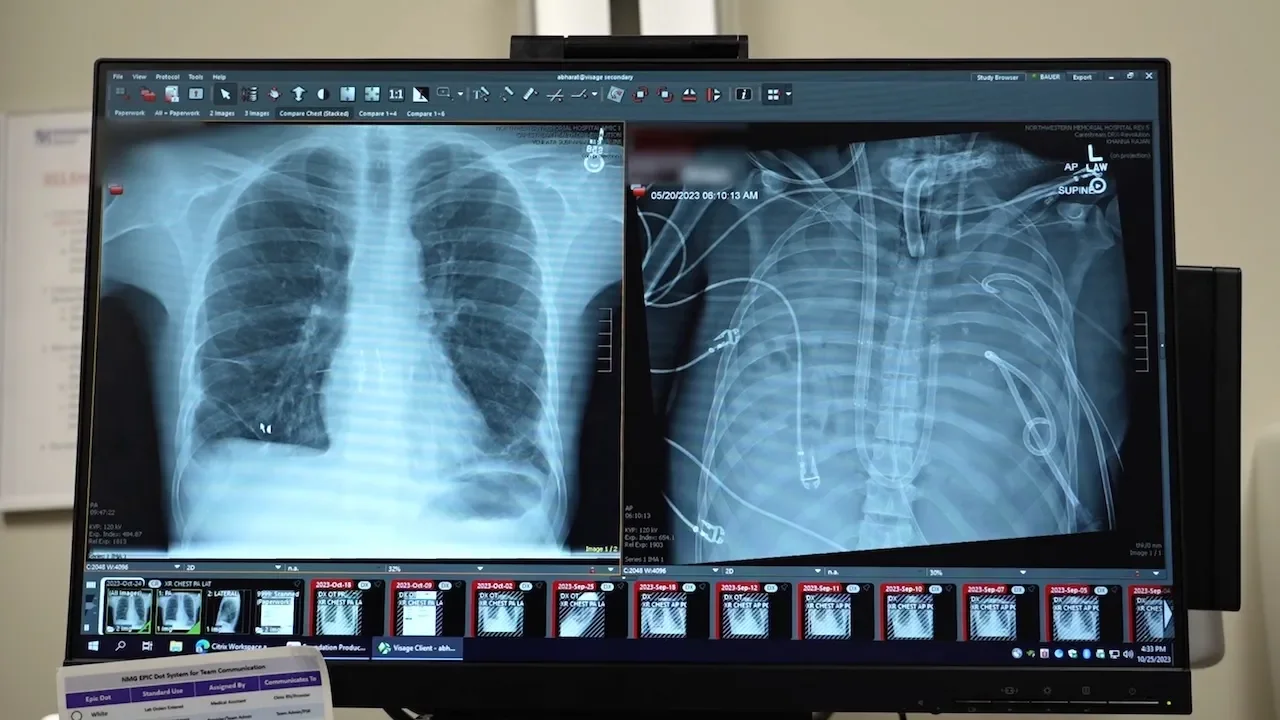

Surgeons at Northwestern Medicine used a total artificial lung system to take over gas exchange after removing both diseased lungs from a critically ill patient, preserving heart function and bridging him to a double-lung transplant. The patient survived 48 hours on life support and, after the procedure, recovered well; two years later he has normal lung function and is fully independent.